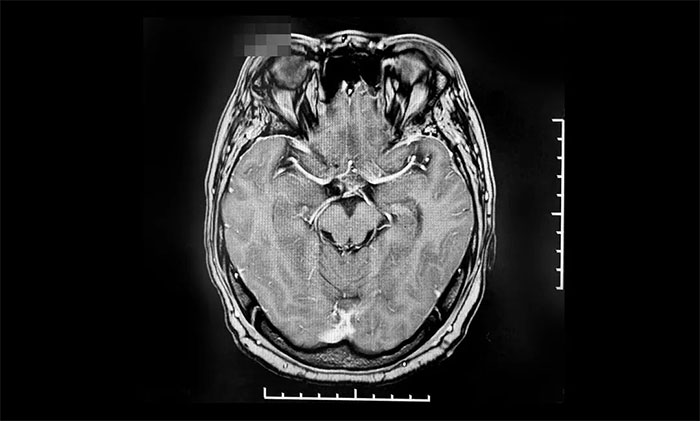

2022年8月,因视力下降就医,复查提示肿瘤复发,遂来上海蓝十字脑科医院进行伽玛刀治疗,后顺利出院。今年10月,患者来院复查,影像学检查提示肿瘤体积较治疗前明显缩小,患者视力较前改善,控制良好,陈琦主任叮嘱其继续随访观察。

▲ 出院14个月后复查影像